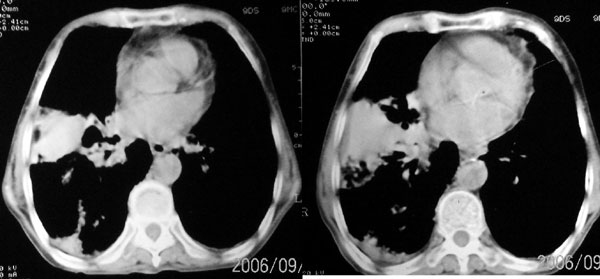

f 76 间断咳嗽 咳痰1年余 发热不明显 身体削瘦

1、右肺中叶近肺门区可见一空洞样病灶,内壁不规则,有与邻近支气管相通的征象,其外侧大片肺组织软组织状实变,余肺可见散在点、片絮状密度增高影,肺纹理可见明显增粗及串珠样改变;

3、右侧胸膜增厚粘连,胸腔少量积液征像;

诊断意见:

1、右侧中央型(空洞性)肺癌并双肺受累(包括转移、阻塞性炎症、癌性淋巴管炎);纵隔、右侧腋窝内淋巴结肿大、转移;右侧胸膜增厚粘连,胸腔少量积液;

2、双上肺陈旧性结核。

3、慢性支气管炎、肺气肿。